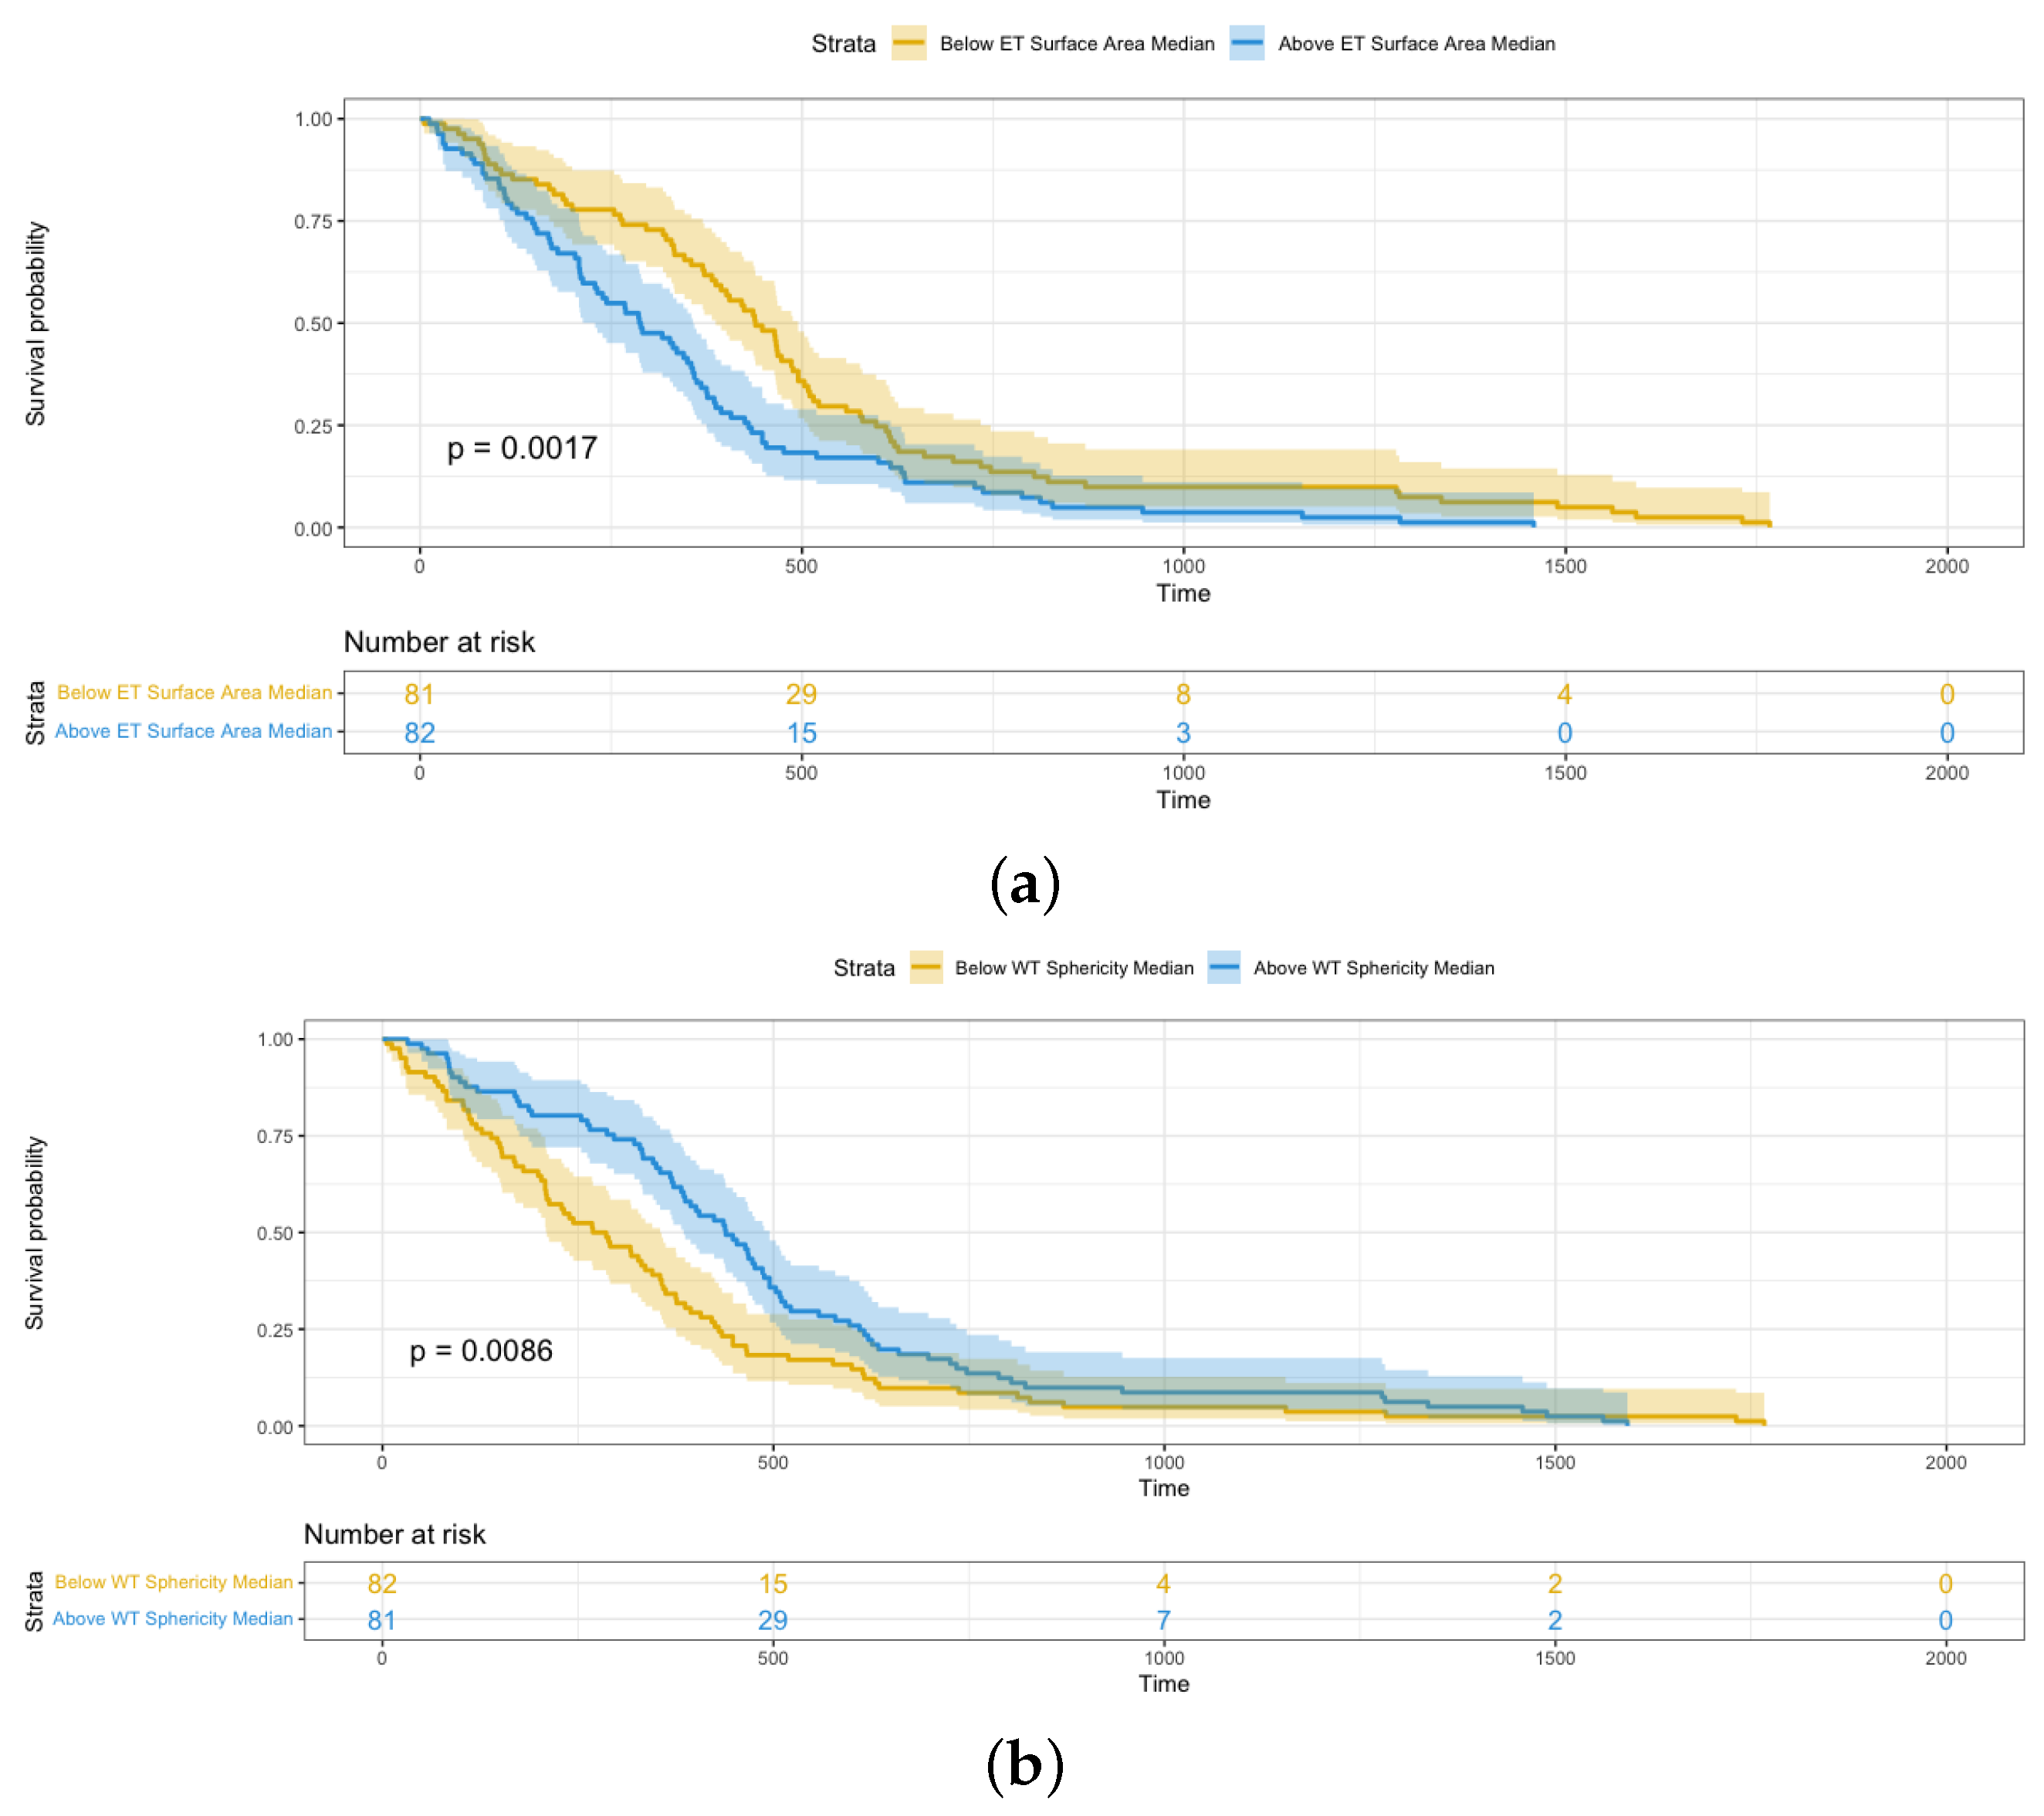

- Sphericity, 3D maximum diameter, and surface area are three significant shape features relevant to the survival analysis of glioblastoma patients. Furthermore, these features from the enhancing tumor have more effect on patients’ survival time than those from the whole tumor based on hazard ratio.

4.3. Shape Radiomics Features Analysis

| Sphericity | 0.184 | 0.049–0.698 | 0.01 |

| Sphericity | 0.2669 | 0.069–0.762 | 0.02 |